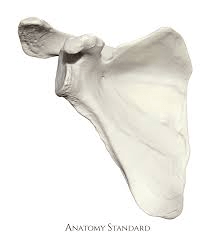

Name the bone AND the side of the body it is from.

Scapula (Right)